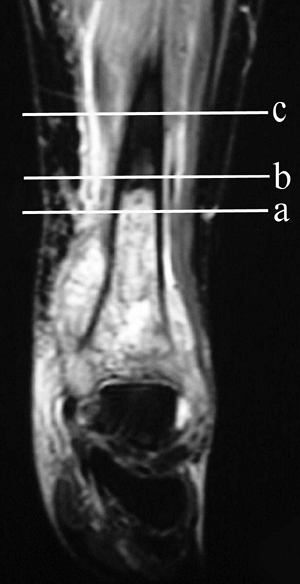

Figure 4.1-2

Magnetic resonance imaging of a high-grade osteosarcoma of the distal

tibia illustrating margins possible obtained at different levels of

amputation: intralesional (a), marginal (b), and wide (c). A radical margin would be obtained with a knee disarticulation. -